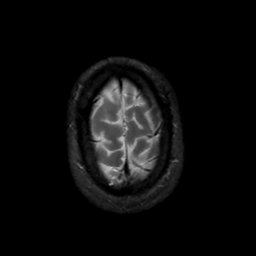

MR Study #14, June 2, 1991 -- Slice #45

[Home][Help][Clinical][Tour 1][Tour 2] Slice 45